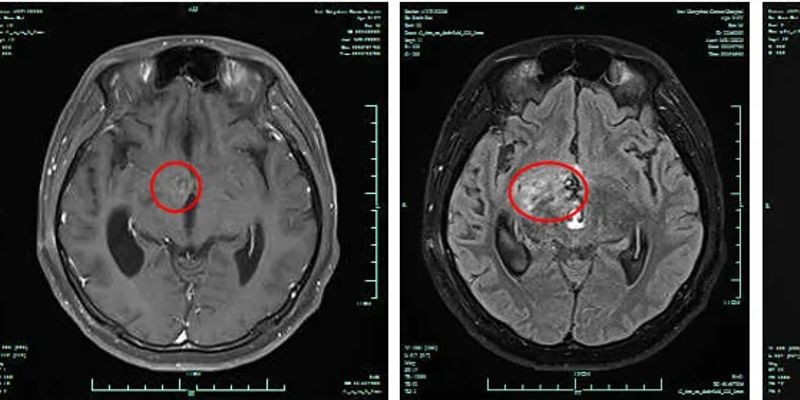

分享一例高级别神经胶质瘤患者的成功治疗经验。在标准治疗后疾病仍快速进展的情况下,采用替莫唑胺(Temozolomide)联合替尼泊苷(Teniposide)的化疗新方案,成功控制了肿瘤进展,实现了病灶稳定。了解这一为神经胶质瘤患者带来新希望的治疗选择,以及该方案的有效性与安全性。 Read More... "神经胶质瘤治疗新选择:替莫唑胺联合替尼泊苷化疗成功案例"